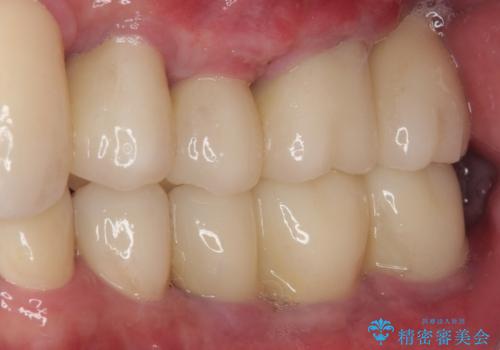

強い咬合力で奥歯がボロボロに インプラント治療による咬合回復と全顎セラミック治療

上顎前歯に歯周ポケットの深い部分がありましたが、インプラントの仮歯で奥歯がしっかりと噛めるようになると、1年程度で深い歯周ポケットは解消されました。

前歯部の審美面も大幅に改善され、大変満足していただけました。